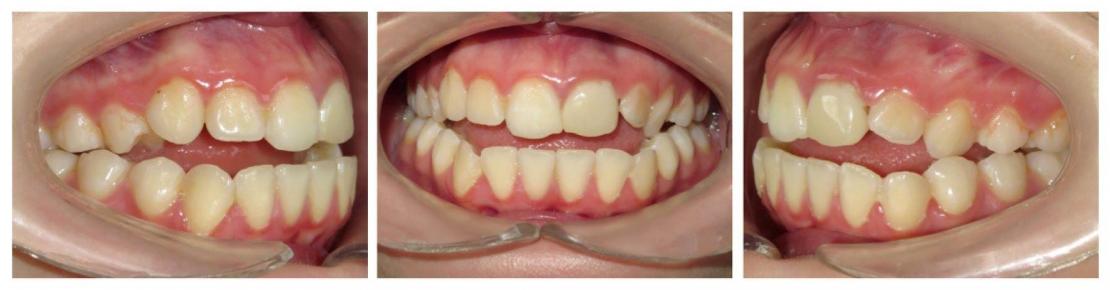

Voici les deux patientes traitées

Ici, dans les deux cas, les deuxièmes prémolaires ont été extraites et les traitements ont duré 18 mois.

Dans le deuxième cas, le désencombrement a fermé les espaces en 6 mois. Les incisives ont été surtorquée pour avoir un meilleur soutien labial. Le traitement qui avait bien débuté, a été difficile à finir, car les anatomies coronaires et radiculaires étaient perturbées.

Si on n'avait pas extrait dans le premier cas, cela imposait une ouverture de l'espace de la 24 et donc une avancée des incisives supérieures et donc une aggravation de la béance. Dans le deuxième, on sortait les racines de l'os alvéolaires (racines déjà apparentes au départ). Même une expansion associée à du stripping et une distalisation des secteurs latéraux n’auraient pas permis de préserver ce parodonte fin.